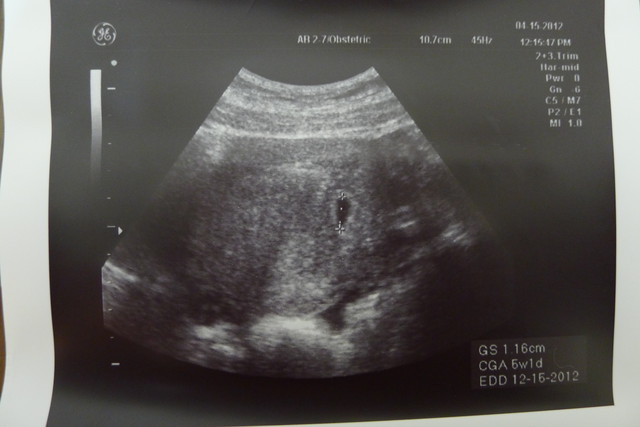

腹部超音波照片(我老公小像蟑螂)